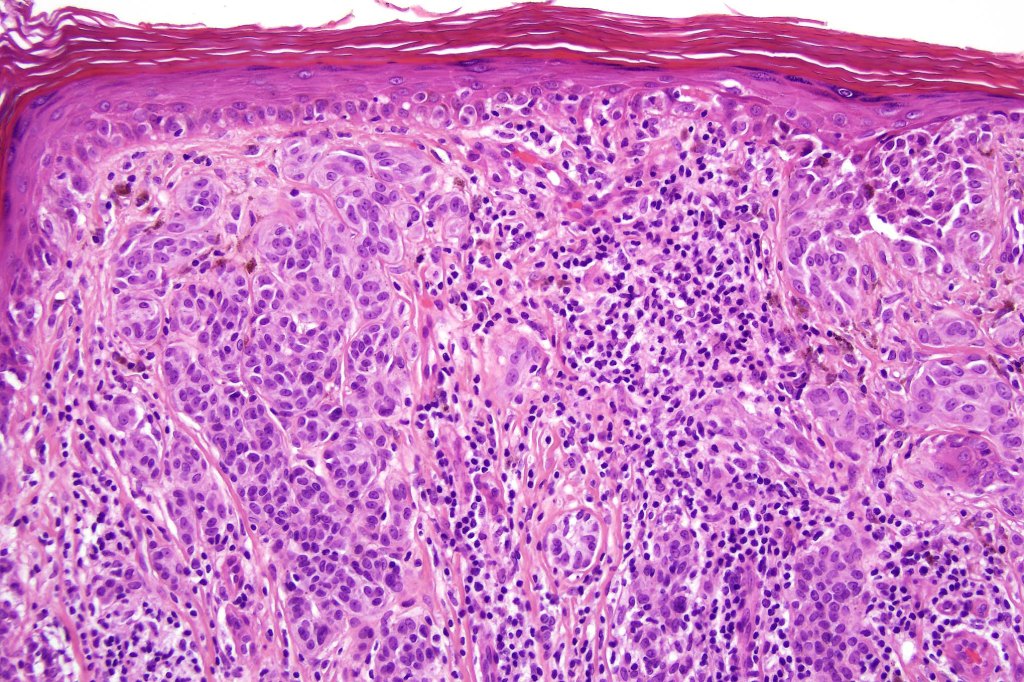

Combined Spitz & common blue nevus